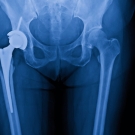

Researchers developed a retrospective cohort study to determine whether conversion total hip arthroplasty (THA) following a failed osteosynthesis leads to higher complication and mortality rates compared...

04/24/2025